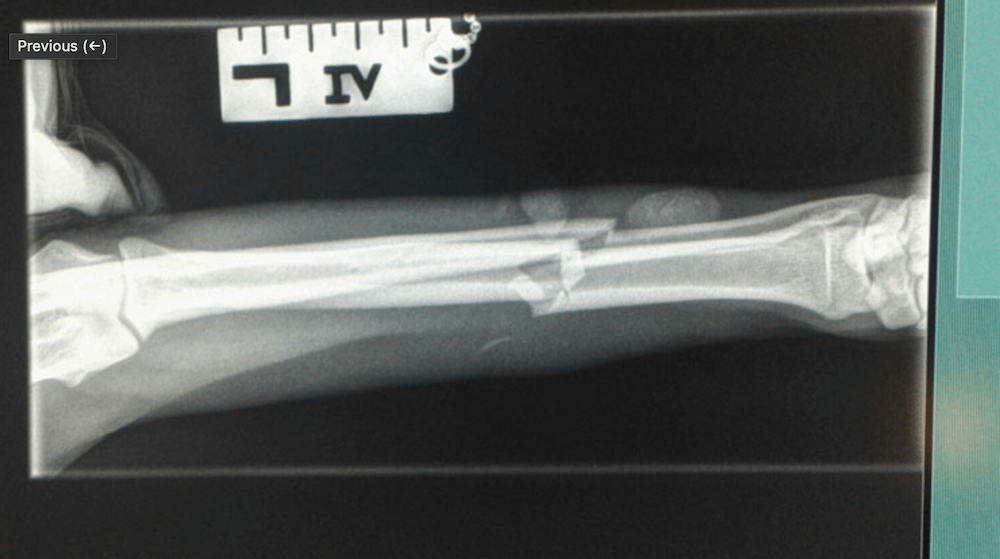

Tibia Fracture Repair